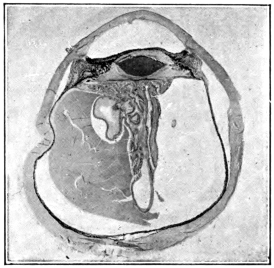

PLATE III.

16.

ABUNDANT EXUDATE INTO VITREOUS CAVITY

curly bracket span

17.

LENS FIRMLY FIXED BY ORGANIZED EXUDATE

18.

LENS FIRMLY FIXED BY ORGANIZED EXUDATE, BUT IN UNUSUAL POSITION

19.

TOTAL DETACHMENT OF RETINA, WITH CYST FORMATION

20.

RECLINED LENS LYING IN FRONT OF THE HYALOID BODY

21.

RECLINED LENS LYING IN FRONT OF THE HYALOID BODYxii